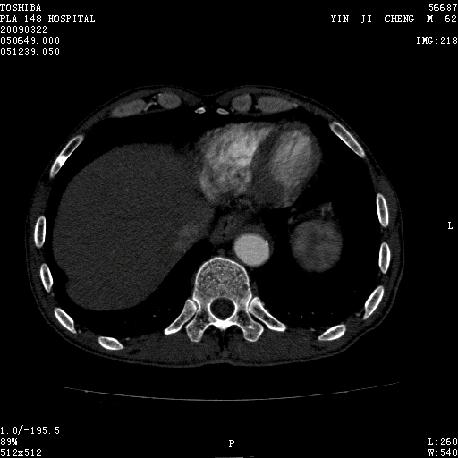

男 62 夜间突然腹痛并向背部放射 ,急诊疑胰腺炎 ,胰淀粉酶正常 ,ct示胰腺未见明显异常,发现降主动脉密度欠均,做主动脉造影示胸腹主动脉半月形低密度充盈缺损,内膜钙化并内移,累及腹腔干致根部明显狭窄,未见明显破裂口。 本人为是不典型夹层,其他人有说是动脉硬化或动脉炎的。请大家发表一下看法。

可惜图像太小,但结合病人年龄、病史及降主动脉壁增厚及模糊表现应该考虑,在我看到的急性主动脉夹层别人中血管壁都有这样改变。

主动脉附壁血栓?主动脉夹层?

我觉得这个不像主动脉夹层,应该是血栓多点,如果可以重建个mpr也许对诊断更有帮助。